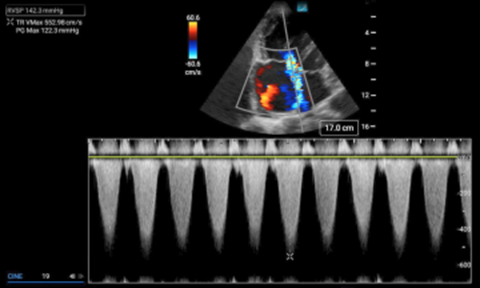

Calculating right ventricular systolic pressure

The right ventricular systolic pressure (RVSP) determined by echocardiography can approximate the pulmonary artery systolic pressure (assuming a normal pulmonic valve). Determining this value is predicated on the ability to measure the velocity of the tricuspid regurgitant jet in an apical four chamber view. To obtain this value, the tricuspid regurgitant jet is first identified in an apical four chamber view (A4C) using color doppler. The eccentric jet shown in Figure 1 highlights the importance of first localizing it with color doppler. Then a continuous wave (CW) doppler line is placed through that jet with the focal zone (diamond) in or near the vena contracta (the thinnest part of the jet close to the valve). The resulting wave form should demonstrate repeating downward parabolas. (Figure 1) Increasing the doppler scale, and adjusting the baseline upwards, may be necessary to avoid aliasing for these high velocity cases. The pressure gradient is then extrapolated by using a simplified Bernoulli equation. In the case of this patient, the velocity measures 5.53 m/s, so the pressure gradient (PG) is about 122mmHg (normal would be zero to trace regurgitation). In cases where the diagnosis of PAH is known, comparing the patient’s historic RVSP value to that on presentation, can be helpful.

Tricuspid Valve Regurgitant Jet Pressure Gradient (PG) = 4V2

PG = 4 (5.53)2 = 122.3 mmHg

Figure 1. Continuous wave doppler measuring the maximum velocity of the tricuspid regurgitant jet (TR Vmax).